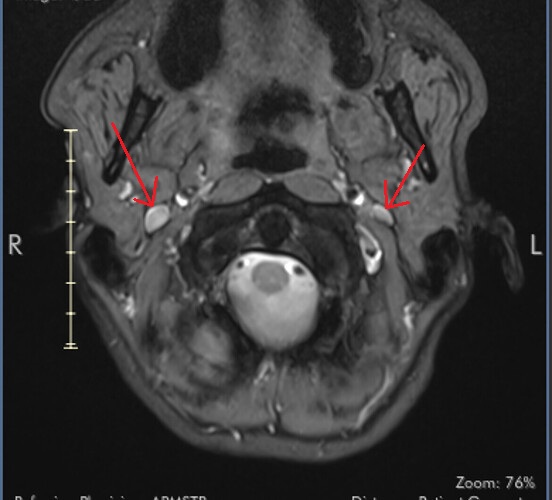

I marked the images for you and marked the IJV.

So you can see how the IJV passes by the transverse processes of C1 which are compressing. In this position the right IJV does not have severe compression, but in Figure 2 you can see that the left IJV is almost invisible, and in the other images there is significant narrowing.

On MRI, it is very difficult to see the styloid processes.